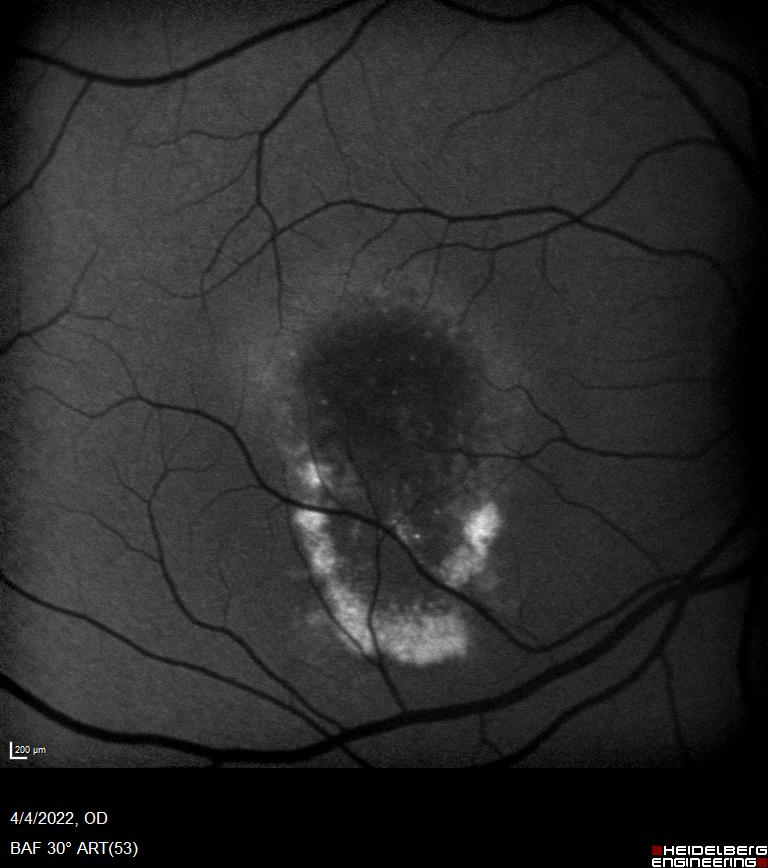

Η συγγενής φυλοσύνδετη ρετινόσχιση είναι μια κληρονομούμενη δυστροφία του αμφιβληστροειδή η οποία οφείλεται σε μεταλλάξεις του γονιδίου RS1. Εμφανίζεται με μείωση της κεντρικής όρασης σε νεαρούς άρρενες. Ο ηλεκτροφυσιολογικός έλεγχος (Ηλεκτροαμφιβληστροειδογράφημα) είναι πολύτιμος για τη διάγνωση της νόσου μιας και έχει χαρακτηριστικά ευρήματα στις καταγραφές ενώ ο γενετικός έλεγχος ταυτοποιεί τη διάγνωση.